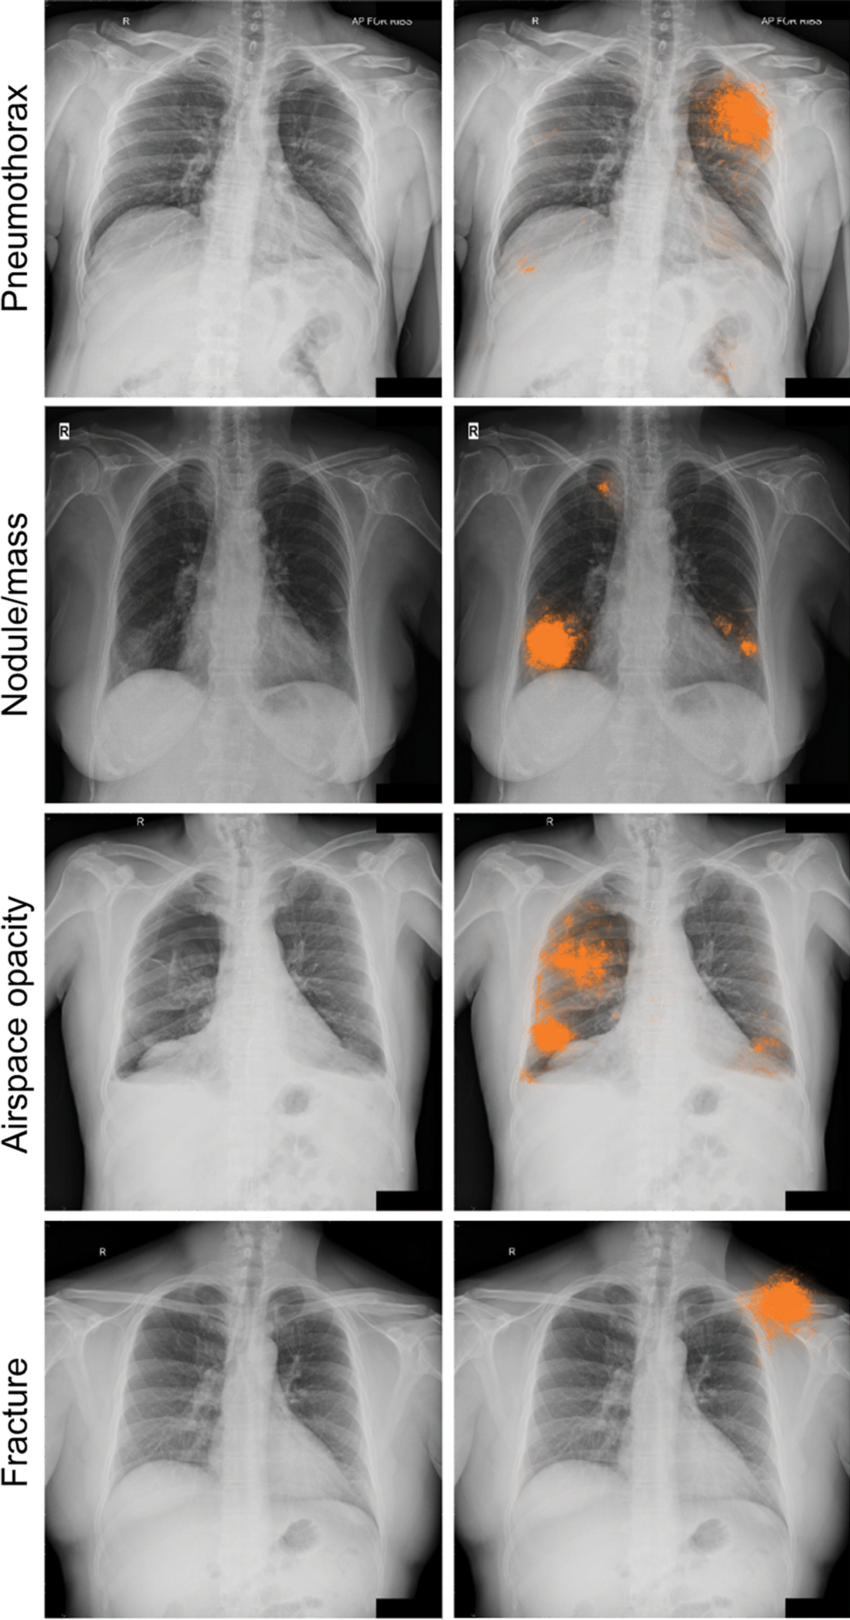

Figure 5a. Radiographic images with discordant interpretations between deep learning models and radiologists. (a) Examples for the four classes of abnormality (pneumothorax, nodule or mass, airspace opacity, and fracture) classified correctly by the deep learning model (ie, concordant with the adjudicated reference standard), but not identified by any of the four radiologists in the performance comparison cohort. The highlighted areas (orange) indicate the regions with the greatest influence on image-level model predictions, as identified by using SmoothGrad (29).